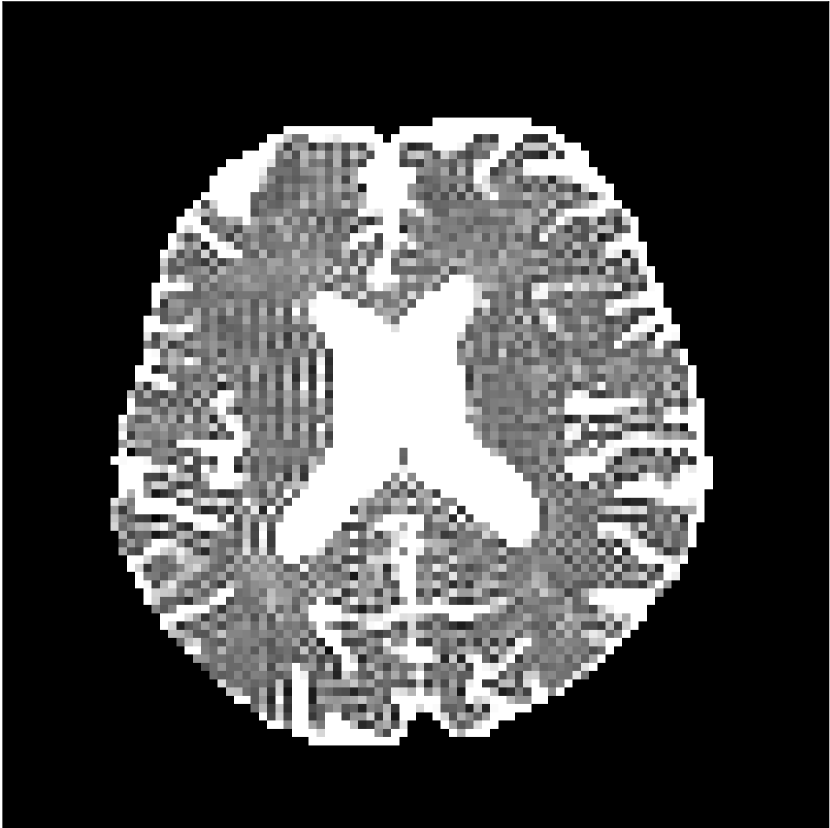

Figure 8 shows examples of non-diffusion-weighted images before and after processing. The raw images (Raw) served as the input for the magnitude deep learning (MCNN) and complex deep learning (CCNN) methods.

Raw 𝐱tsubscript𝐱𝑡\mathbf{x}_{t}

MCNN, fθ^(𝐱t)subscript𝑓^𝜃subscript𝐱𝑡f_{\hat{\theta}}\left(\mathbf{x}_{t}\right)

MCNN Resid., Ric(𝐱t)fθ^(𝐱t)Ricsubscript𝐱𝑡subscript𝑓^𝜃subscript𝐱𝑡\text{Ric}(\mathbf{x}_{t})-f_{\hat{\theta}}\left(\mathbf{x}_{t}\right)

CCNN, fθ^(𝐱t)subscript𝑓^𝜃subscript𝐱𝑡f_{\hat{\theta}}\left(\mathbf{x}_{t}\right)

CCNN Resid., Ric(𝐱t)fθ^(𝐱t)Ricsubscript𝐱𝑡subscript𝑓^𝜃subscript𝐱𝑡\text{Ric}(\mathbf{x}_{t})-f_{\hat{\theta}}\left(\mathbf{x}_{t}\right)

No PF

5/8 PF

Figure 8: Examples of non-diffusion-weighted images from in vivo data at b=0𝑏0b=0 s/mm2. Artifacts in the Raw image, 𝐱tsubscript𝐱𝑡\mathbf{x}_{t}, are corrected by the MCNN and CCNN models, fθ^(𝐱t)subscript𝑓^𝜃subscript𝐱𝑡f_{\hat{\theta}}(\mathbf{x}_{t}). Also shown are the residuals between the CNN corrections and the original Raw image with Rician bias correction Ric(𝐱t)Ricsubscript𝐱𝑡\text{Ric}(\mathbf{x}_{t}) [10]. The Gibbs artifacts removed by the methods are observed in the residuals. The MCNN method introduces some banding artifacts at the PF 5/8ths factor that are not present in the CCNN method.

Both methods remove artifacts, but the MCNN method allows residual rippling artifacts to pass through in the presence of partial Fourier. These rippling artifacts are not present in the CCNN method.